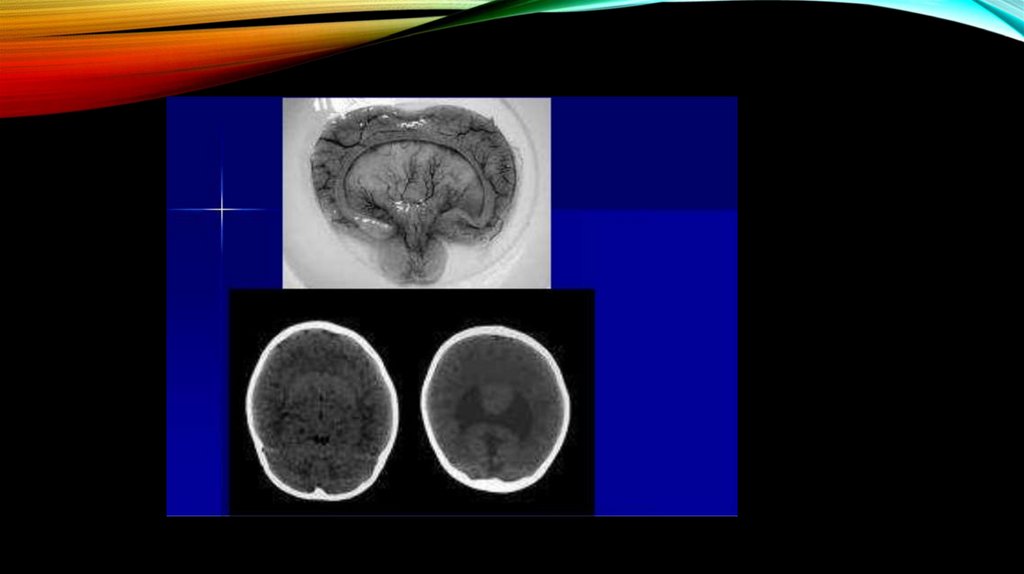

Phylogenetic Disorder of Neocortex

Phylogenetic disorders of brain

Phylogenitic disorders of CNS